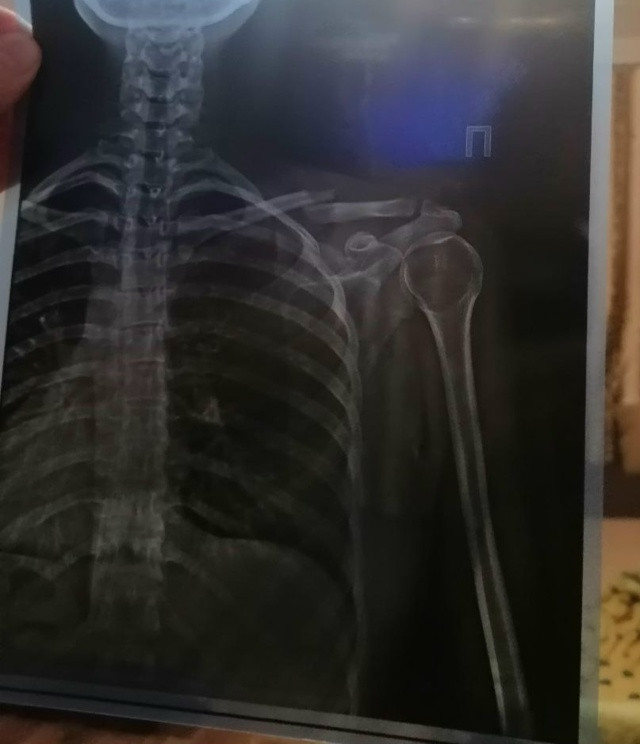

Сегодня обратилась в травмпункт и после рентгена обнаружили перелом ключицы со смещением (фото прикладываю), обозначили,что нужно делать только операцию, дали направление на экстренную госпитализацию в больницу ГКБ им Гринберга на ул.Ардатовская 40. Приехала туда по вызову скорой помощи..Принимает меня,значит,врач (в медицинском заключении в котором он меня,мягко говоря,послал).. Смотря на меня начал мне грубо говорить-"Ну сходила ты в травмпункт зачем ты на скорой помощи сюда приехала? Ты понимаешь,что они из за тебя на вызов важный не поехали?" Я в полном шоке,ниче не понимаю с какого фига на меня такая агрессия. Если у меня экстренная госпитализация я должна была сама к ним прикатить как оказалось. Дальше он смотрит мой снимок, щупает мою лопатку и говорит-"Я здесь не вижу повода для операции" купи себе реклинатор и иди в свой травмпункт,тебе там её оденут правильно..10 дней ходи,потом сделаешь рентген,там будет типа процесс заживления и продолжай ходить в ней до полного сращивания кости. Дали мне мединское заключение,где не подчеркнута причина отказа от госпитализации,где сказано лишь-дата явки в травмпункт 20.09.25 и послали меня домой. Хочу узнать,может кто то сталкивался с этим врачём и тоже огрёб от его хамского поведения? Я думаю и врачом быть ненадо что бы понять,что моя кость не срастётся под "бинтиком"..Расскажите кто сталкивался с этой больницей и её врачами,и как вам там отношение к себе..а если вы лечились у коробейникова было бы интересно узнать его отношение ко всем пациентам было такое же как ко мне или нет